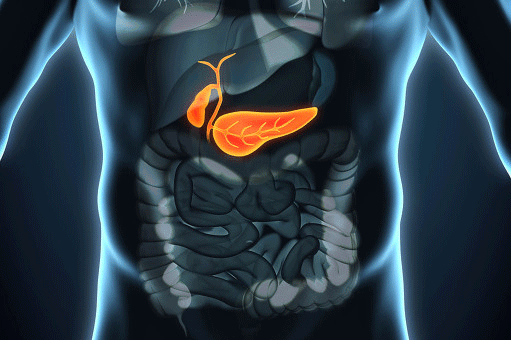

胆嚢の大きさは?胆嚢の大きさは5~8cmで、右上腹部にある、普段よく目にするお金袋のような形をしています。肝臓の下には特別な胆嚢窩がある。。

胆嚢という臓器は、私たちの体にとってどのような役割を果たしているのだろうか?胆嚢は、一見誰もが思っているように、実は胆汁を分泌する場所ではありません。胆嚢の役割は、肝臓から分泌された胆汁を受け取り、貯蔵し、濃縮し、胆管内の圧力を調整することです!私たちが通常30分以内に何かを食べるように、胆嚢は自分自身の濃縮された胆汁を腸に排出し、腸が脂肪や他の食物を消化吸収するのを助ける。

これに加えて、胆嚢には自己防衛の役割もある。胆嚢は漿膜、筋層、固有層、粘膜の4層に分かれている。そのひとつがこの粘膜層で、先ほど述べた強力な吸収・濃縮機能に加え、粘液を分泌して他の外的要因から胆嚢を守る粘膜細胞の層がある。

胆嚢は肝臓の下端にある人体の臓器で、胆汁を貯蔵・濃縮する袋状の構造をしており、食物を摂取すると十二指腸に排出され、脂肪の消化・吸収のプロセスに関与する。